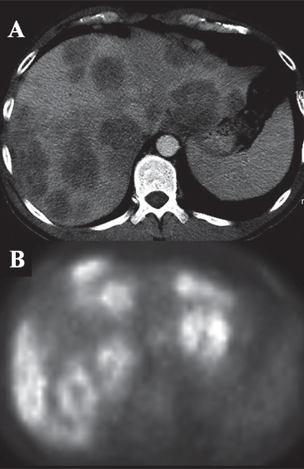

Patient with extensive hepatic colorectal metastases on CT (A) and FDG-PET (B)